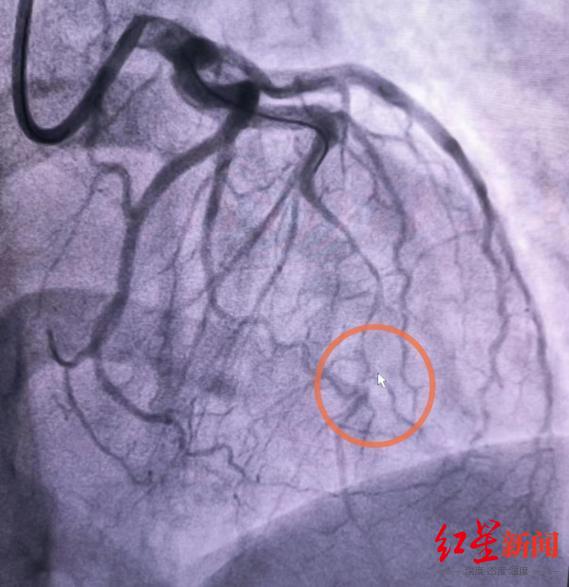

成都市第三人民医院是西南地区首家获得认证的“国字号”胸痛中心,拥有完善的急救“绿色通道”。王女士在被医护团队飞速护送至导管室后,心血管内科夏茏、叶滔、陈中波三位医生组团配合,以最快速度为其完成了冠脉造影检查。结果提示:“前降支重度狭窄,血管中段出现血管不光滑改变”。

血管表现出“断层式的狭窄”,这不是常规的动脉粥样硬化疾病表现。在迅速判断后,心血管内科胸痛急诊团队又为王女士开展了腔内影像学IVUS(冠状动脉血管内超声)进一步检查并精准找到了病因——前降支血管夹层影像,俗称自发性冠脉动脉夹层(SCAD)。简单来说,就是血管内壁有撕裂,漏出的血液被尚还完好的血管外壁兜着,犹如自行车胎“鼓包”。

通过冠状动脉血管内超声检查,医生找到了王女士血管夹层破口的位置,并对血肿对管腔的压迫情况及残存管腔情况进行了判断。夏茏介绍说,自发性冠状动脉夹层是一种较为罕见的心血管疾病,可因形成的血肿压迫血管引发心梗,其死亡率却高达为70-75%,“好在夹层破口撕裂到中远端就停止了,血肿未完全压迫血管,心梗的程度较轻微。”基于完善的检查结果和综合判断,目前暂时可以不作介入支架治疗干预,待自身血肿慢慢吸收和夹层逐渐愈合。不过,需要同步接受密切观察,警惕血管问题进一步加重。